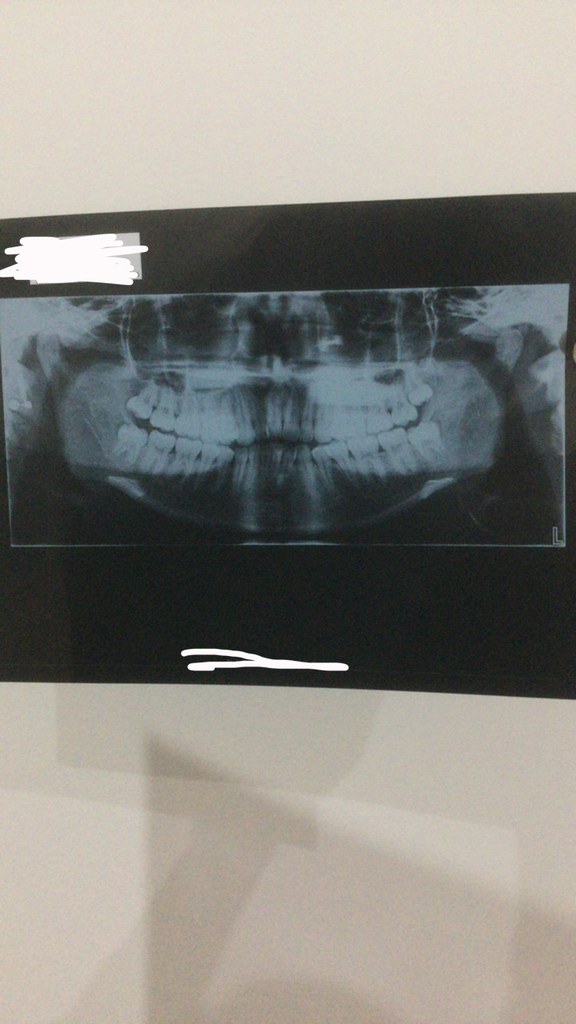

Okay so I went to my ortho today, he was looking at my teeth, said all the right things (crowding, 9mm overjet, severe class 2 malocclusion, crossbite),

I also told him I have sleep apnea and I did 2 scans but here’s what he told me, he told me he can’t offer me MARPE and that my two options would be

Anyways I underwent an OPG and a Cenograph, these are the results.